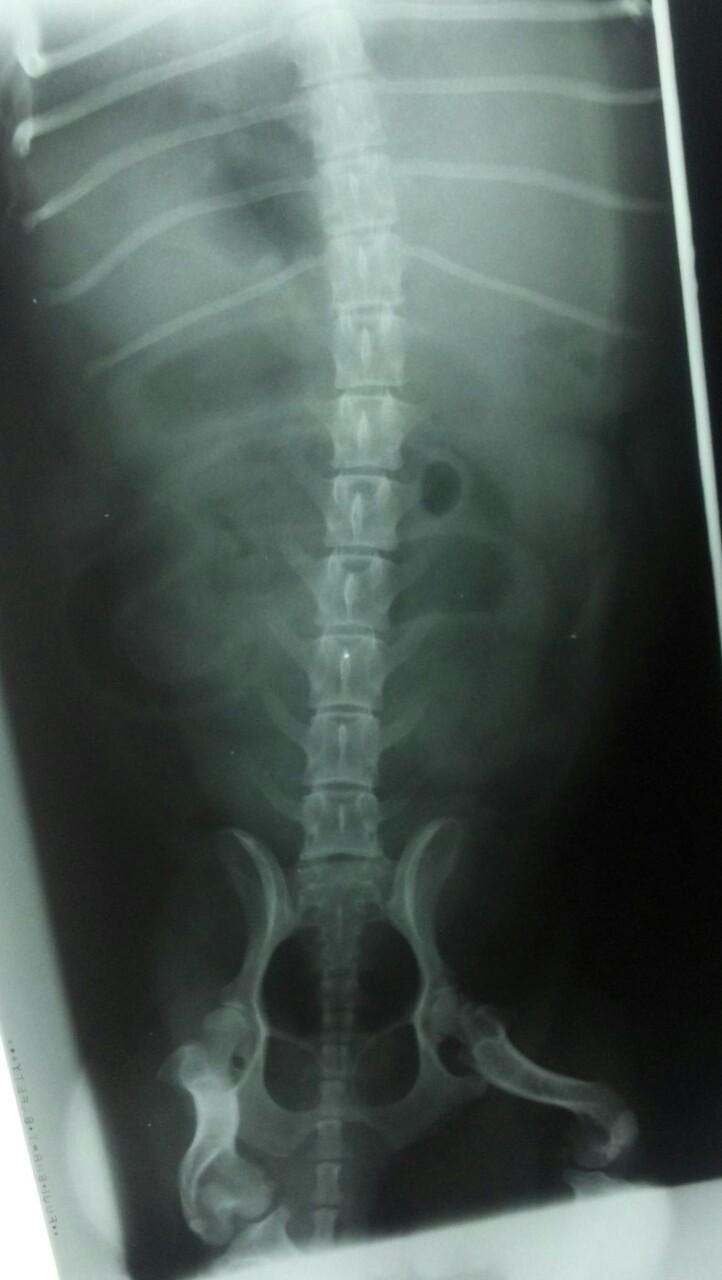

The patient is a 13 year old spayed female Dachshund dog which was presented for four days of anorexia and vomiting. She was given Cerenia, which helped, but still had ileus. Dog has vomited carpet material in past. Spec cPL was normal. Radiographs revealed dilated intestine, which appeared to be colon and cecum.